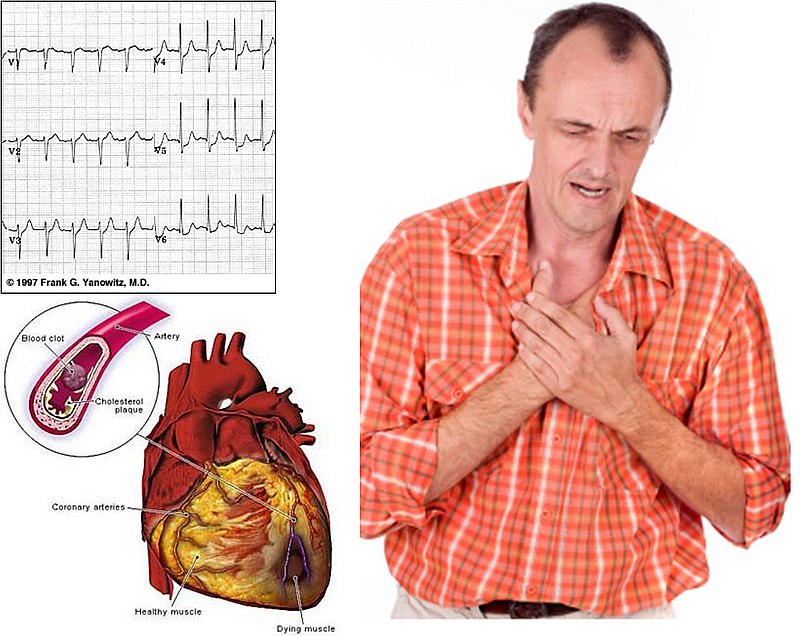

Los ataques del corazón fueron considerados los causantes del mayor número de muertes alrededor del mundo. En los últimos años las cifras han descendido considerablemente gracias al nivel de información que se ha viralizado por todos los medios de comunicación y redes sociales.

Sin embargo, siguen muriendo personas y es necesario seguir informando sobre los síntomas que presenta nuestro cuerpo cuando estamos a punto de sufrir un paro cardíaco.

Muchos ignoran el hecho de que el cuerpo de algunas señales un mes antes de sufrir un ataque cardíaco. Suelen ser tan comunes que se confunden, pero cuando aparecen de forma concurrida no debe quedarnos ninguna duda y tenemos que ir con un médico lo antes posible.

8 señales de que estamos a punto de sufrir un paro cardiaco

Arritmias

Cuando la pulsación se vuelve muy irregular es muy peligroso, de hecho, es una de las señales más comunes de un infarto. Puedes sentirte mareado, cansado e incluso con dificultad para respirar.

Mareos

Es muy común que este síntoma se presente antes de un paro cardíaco al igual que la sudoración fría. La sangre debe distribuirse por todo el cuerpo, cuando no lo hace correctamente afecta la temperatura de varias áreas del mismo y genera malestares cerebrales graves.

Presión en el pecho

Sientes como si tuvieras a alguien sentado encima de tu pecho y no puedes quitar esa sensación de allí, te sientes ahogado, con miedo y desesperado. Es la principal señal de falla cardiaca severa.